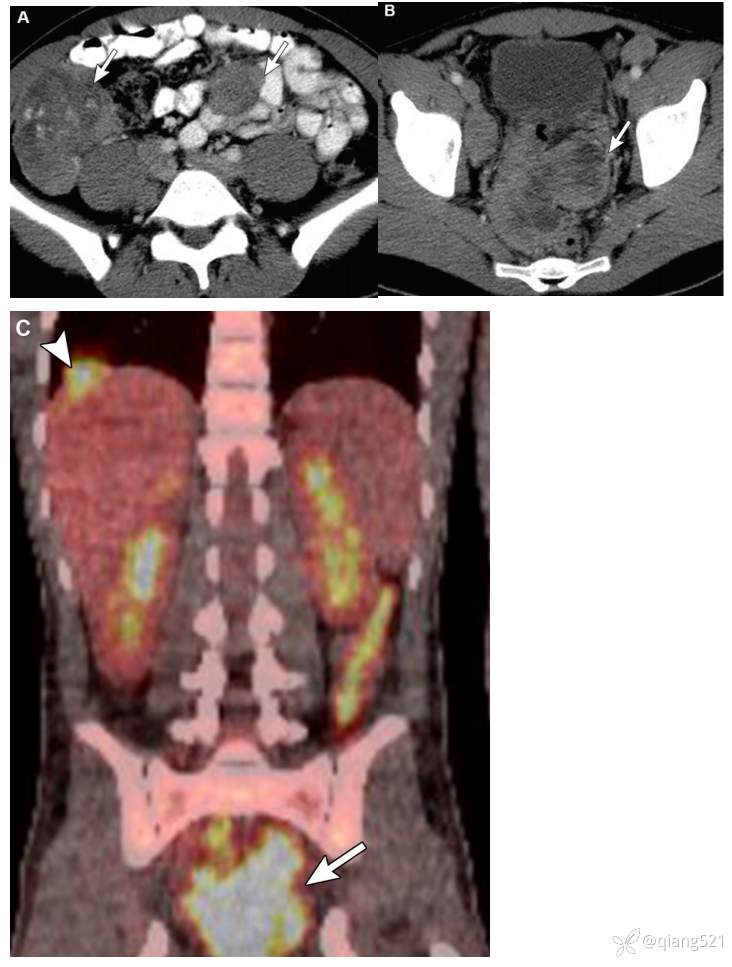

49岁男性腹膜淋巴瘤患者。

A轴位和B冠状位CECT显示右腹部一模糊的软组织肠系膜肿块(箭头)伴腹膜增厚(箭头)。